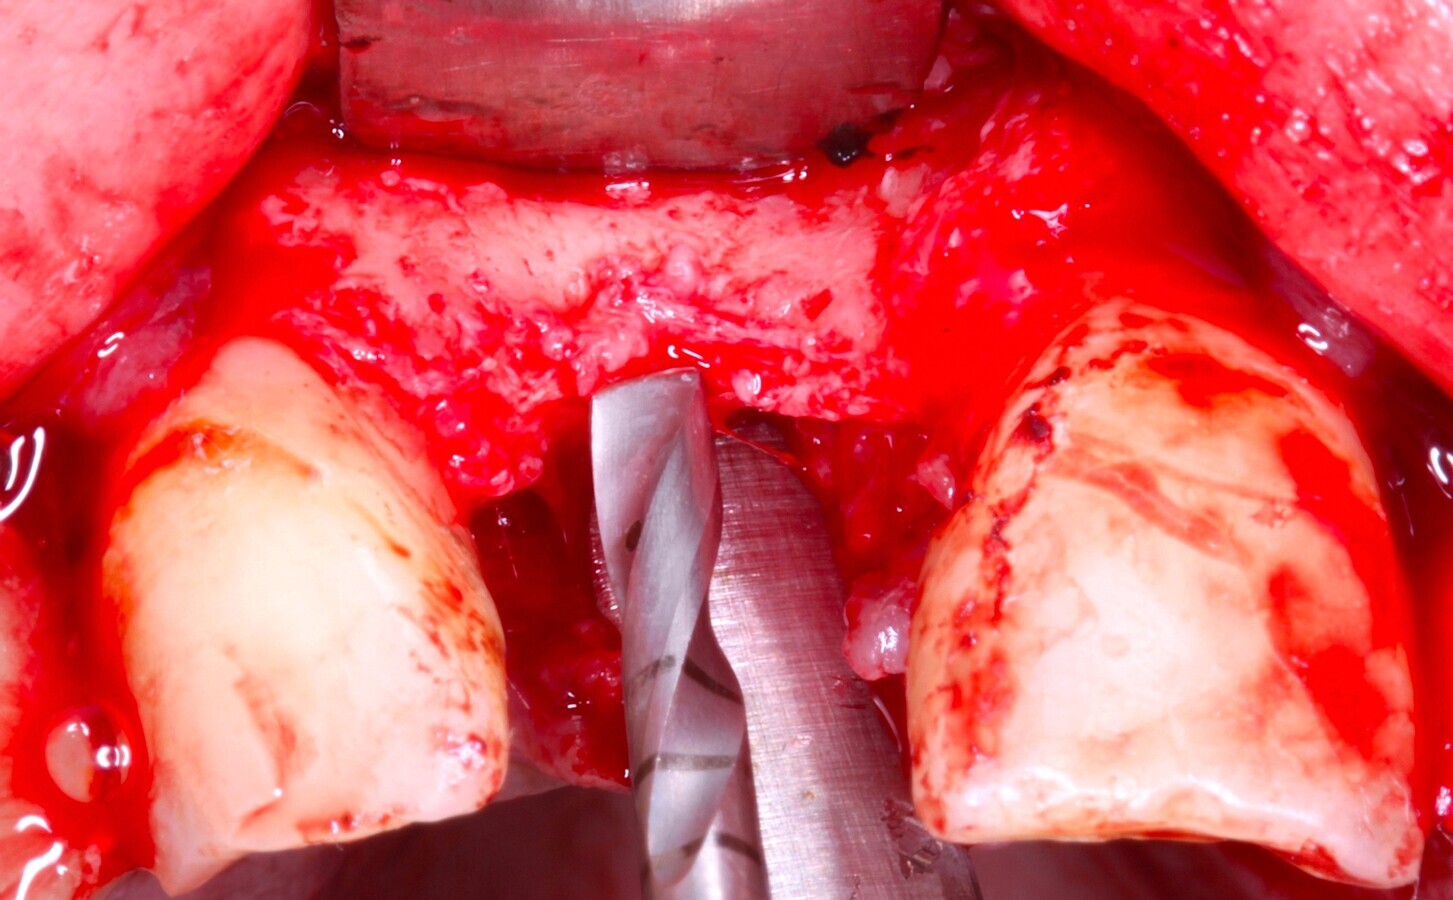

Fig. 9 Figura 9

1. Determinación de la posición del implante con la ayuda de férula quirúrgica y con una fresa redonda o lanceolada.

2. Continuar con el protocolo de fresado estándar.

Fig. 10 Figura 10

1. Inserción del implante, con una estabilidad primaria correcta y posición prostodóntica ideal.

2. Realización de perforaciones en el lecho con fresa redonda para aumentar la disponibilidad de células osteogénicas y acelerar la revascularización y mejorar la unión injerto huésped.